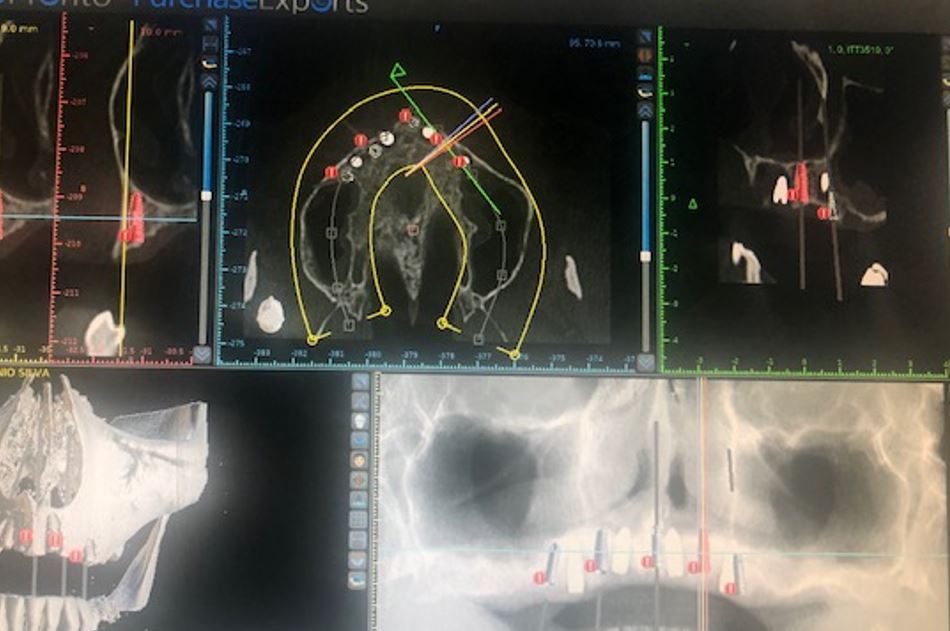

IMPLANTOLOGIA

Nesta área da cirurgia, procedemos à substituição dos dentes perdidos através de implantes dentários certificados. Realizamos cirurgias guiadas, minimamente invasivas, para garantir um maior conforto do paciente.